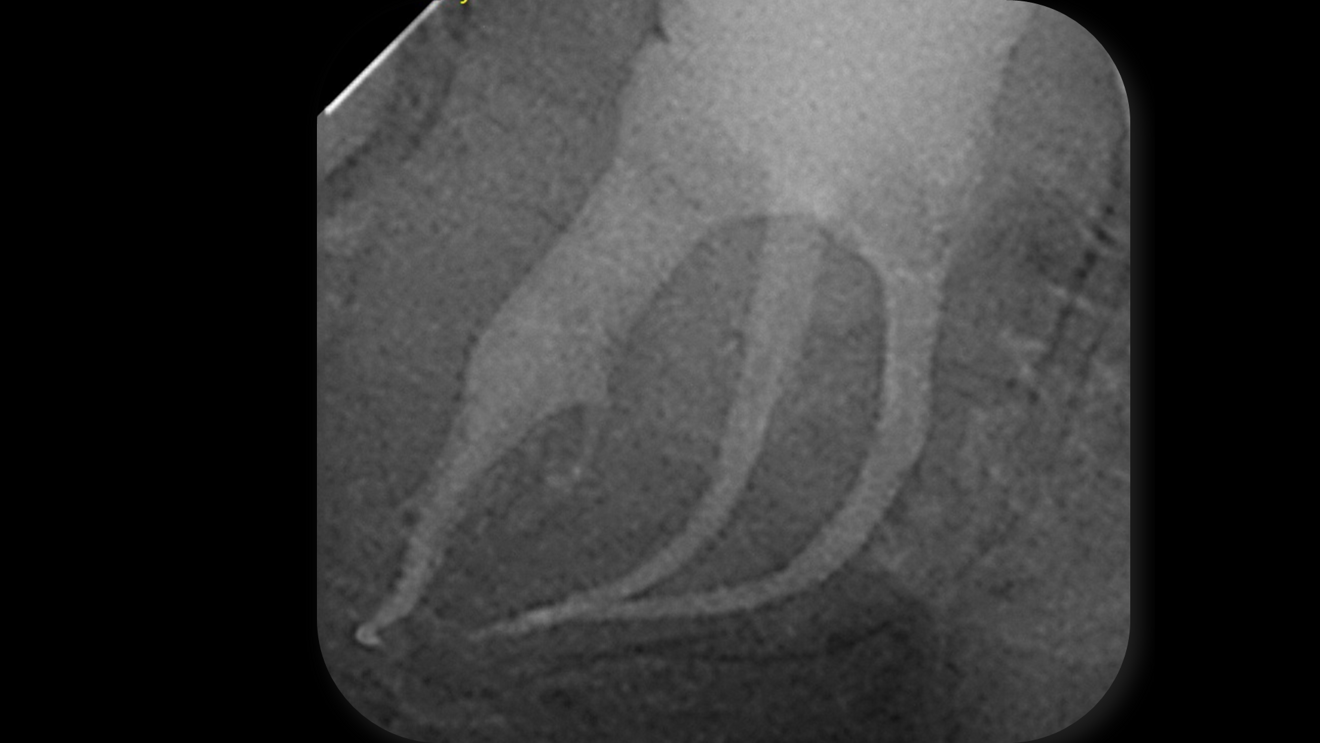

Fig. 1: Pre-op radiograph of the mandibular right second molar showing deep caries beneath the existing restoration and a complex, curved root canal anatomy.

A 19-year-old female patient presented with slight dental anxiety and symptoms of irreversible pulpitis affecting her mandibular right second molar. Under magnification, the existing restoration and carious dentine were carefully removed. The tooth was deemed restorable—strategically important for maintaining occlusal stability in a young patient—and endodontic therapy was indicated. The presence of three highly curved canals posed a particular challenge for both navigation and instrumentation (Fig. 1). The treatment objective was to preserve the tooth while minimising stress and chair time for the anxious patient.